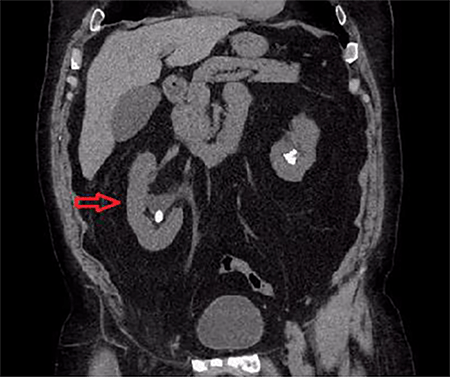

A 67-year-old male with history of hypertension, dyslipidemia, obesity, osteoarthritis, and chronic non-obstructing bilateral nephrolithiasis presented to the emergency department (ED) with a two day history of diffuse abdominal pain. He had associated polydipsia, polyuria and generalized fatigue. The patient reported the presence of chronic inguinal hernias bilaterally, which were asymptomatic and reducible for the last twenty years. During his ED evaluation he denied fever, chills, or changes in bowel habits. He did report hematuria and right sided flank pain with exertion, which he attributed to his known nephrolithiasis. The patient was afebrile and vital signs were within normal limits. Physical examination was remarkable for significant right scrotal swelling consisting of an incarcerated inguinal hernia. In addition, a reducible left inguinal hernia was present. Objective laboratory data included a complete blood cell count and liver function tests, which did not reveal any abnormalities. A renal function panel revealed an increase in the creatinine level to 1.6 mg/dL from his baseline of 0.9 mg/dL that had been constant for the past year. Given his history of nephrolithiasis with acute renal failure, the ED staff along with the medicine team decided to perform a non-contrast computed tomography (CT) to evaluate for acute urinary tract obstruction secondary to stones. The CT scan revealed the following findings: Bilateral fat-containing inguinal hernias, with the right side being larger than the left side, and interestingly, containing the right ureter, which was mildly dilated and extended into the hernia sac (Figure 1). Additionally, retroperitoneal and extraperitoneal fat extended also into the right inguinal hernia (Figure 2). The ureter distal to the sac was decompressed at the level of the internal ring, which raised the concern for incarceration of this portion of the ureter (Figure 3). Finally, the CT also revealed bilateral non-obstructing renal and bladder calculi with significant right sided hydronephrosis that was likely due to the incarcerated ureter (Figure 4).

Figure 4. Coronal view of same study showing bilateral renal calculi with significant right sided hydronephrosis